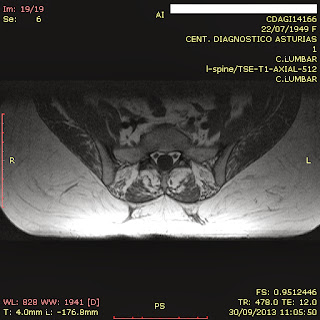

RM_Lumbar (30-09-13): Catastrófica. Discopatía Lumbar (y de toda la CV) Degenerativa, con Masa Ocupante de Espacio del Canal Vertebral, de origen discal, situada en toda la extensión de estos. Rotación I/D con centro superior a L4/L5. Rectificación del plano sagital. Proporción músculo/grasa tendente a cero.

RM_Lumbar